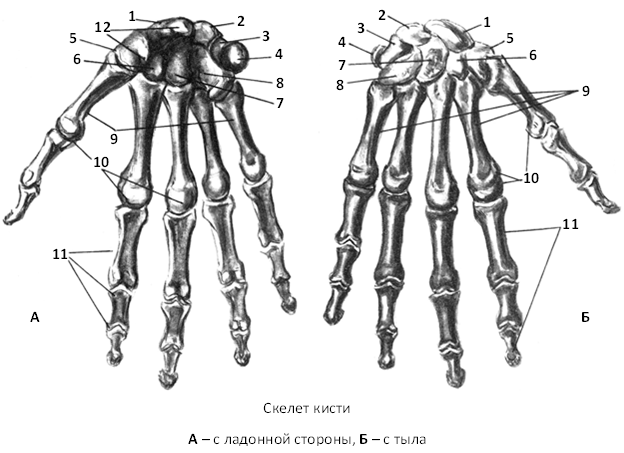

Анатомия кисти руки и строение костей